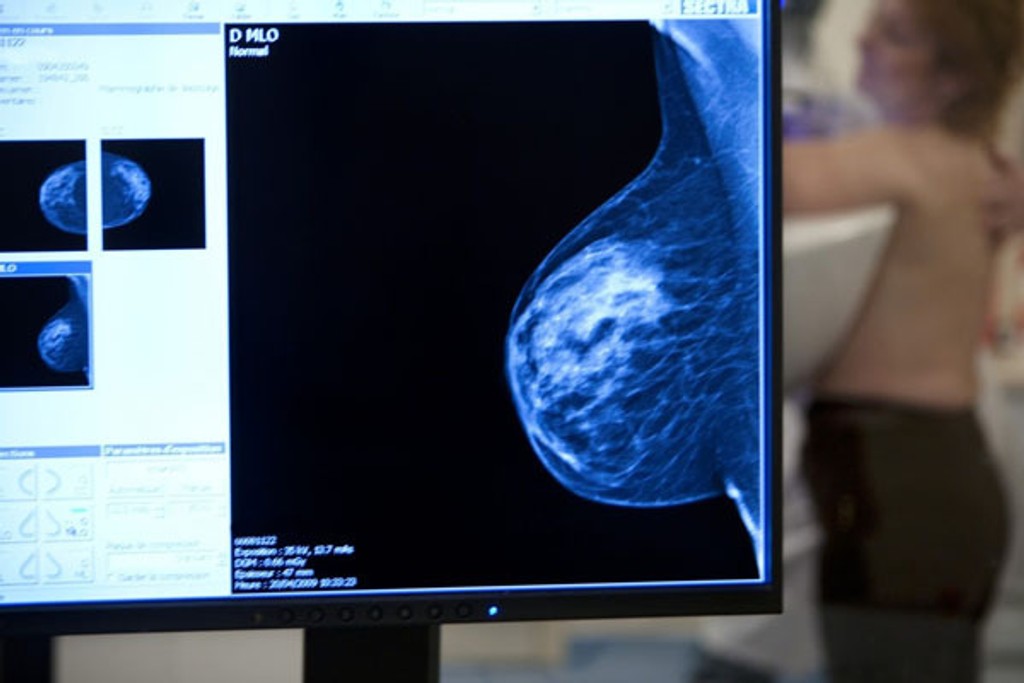

Štúdia spochybnila význam mamografického vyšetrenia prsníka

Vyšetrenie prsníka

Rozsiahla kanadská štúdia spochybnila význam preventívneho vyšetrovanie mliečnej žľazy u žien. Mamografické vyšetrenie síce zachytí nádor včas, avšak podľa štúdie je úmrtnosť na rakovinu prsníka u žien, ktoré screening prekonali, rovnaká ako u tých, ktoré ho nemali. Výskum trval zhruba 25 rokov a zapojilo sa do neho 90 -tisíc žien.

Štúdia, ktorú minulý týždeň zverejnil časopis The British Medical Journal, náhodným spôsobom vyberala Kanaďanky, ktoré potom pravidelne podstupovali mamografické vyšetrenie, vyšetrenie prsníka v ordinácii, alebo si ich vykonávali samy.

Výskumníci chceli zistiť, či je výhoda v tom, keď sa rakovina prsníka zistí vo fáze, kedy je nádor tak malý, že sa nedá ani nahmatať. Došli ale k zápornej odpovedi.